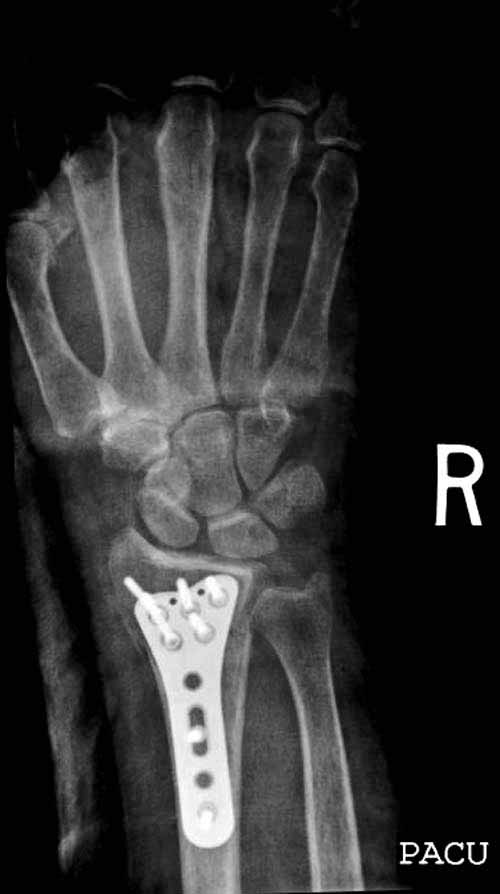

Сегодня все компании: Synthes, Stryker, Zimmer, Acumed, TriMed и т.д. имеют пластины для фиксации дистального перелома лучевой кости. На снимке метод фиксации дистальных переломов, справа Stryker, а слева пластина Synthes,

женщина 58 лет, политравма.